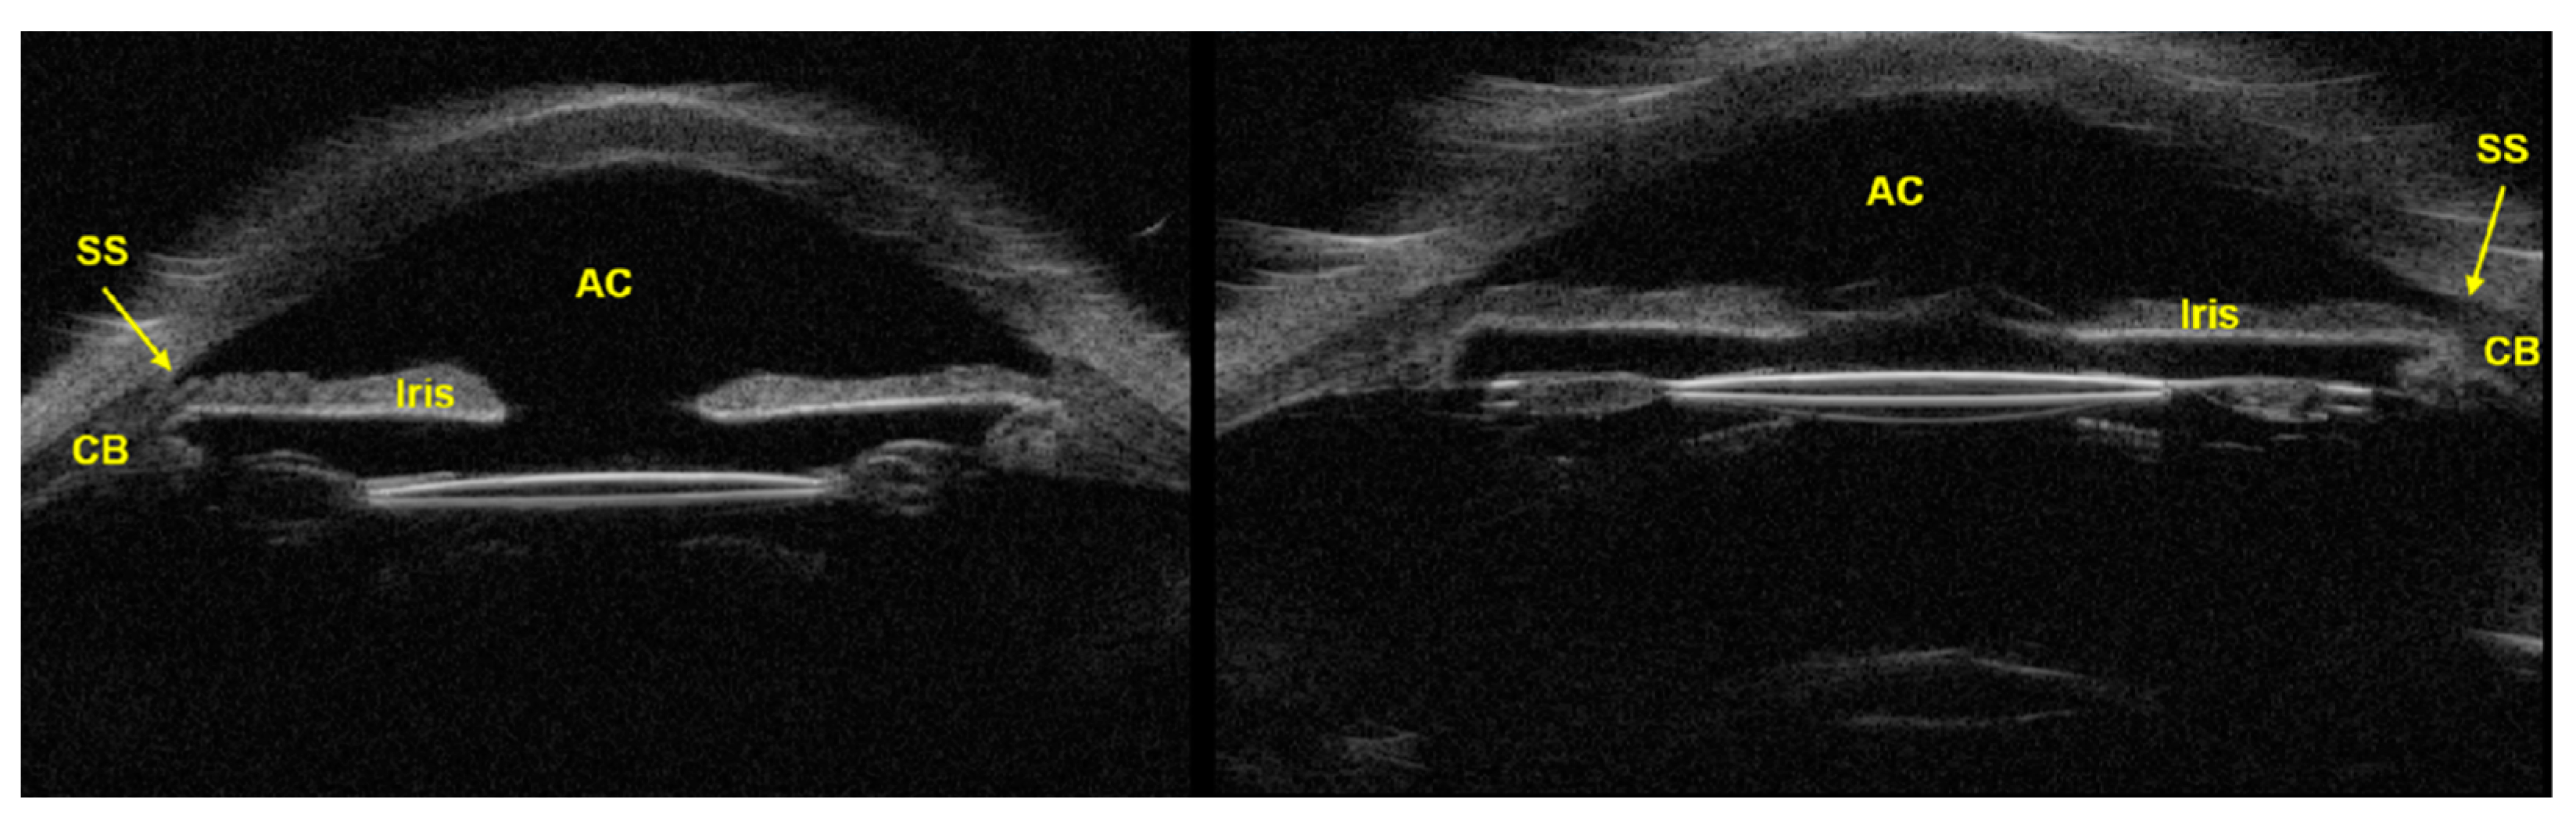

3.2. Ultrasound Biomicroscopy (UBM)

3.3. Anterior Segment Optical Coherence Tomography (AS-OCT)